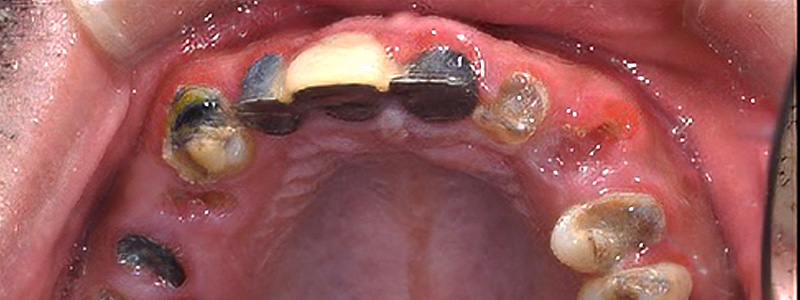

- 治療名

- インプラント治療ジルコニアクラウン

- 治療内容

- 左右臼歯にインプラント治療を行い、残存歯にジルコニアクラウンを製作。

- 患者様

- 40代男性

- 治療期間

- 約9ヶ月

- 費用

- ¥3,146,000

- 治療に対するリスク

- 外科治療に伴う術後疼痛合併症のリスク

- 執刀医

- Dr.村尾